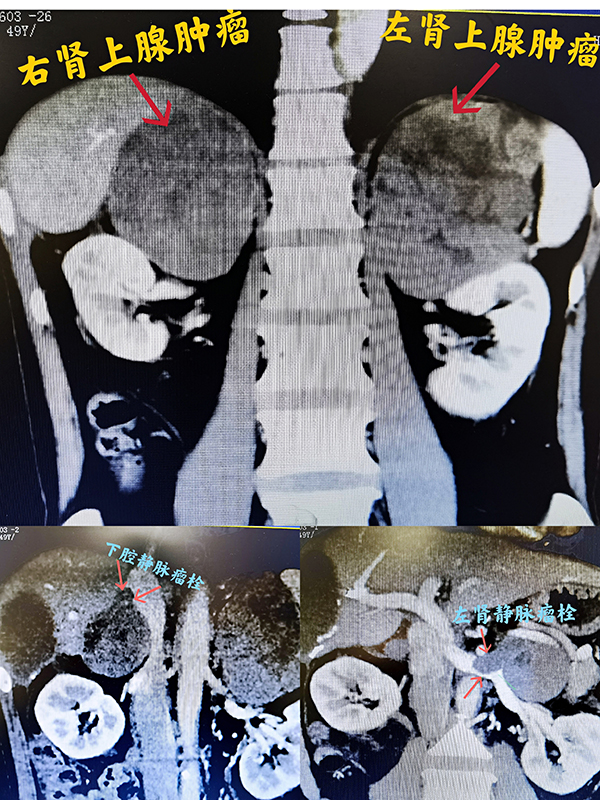

49岁的刘先生是湖南衡东人,2019年9月被诊断为肝癌做了根治手术,可不到1年便发现双侧肾上腺分别长了一个乒乓球大小的转移瘤。尽管立即接受了规范的化疗、免疫及靶向治疗,但肿瘤仍在8个月后疯长到火龙果大小,形成下腔静脉、左肾静脉及双侧肾上腺静脉瘤栓,并广泛累及侵犯右肝、膈肌、左肾及肾动静脉等多个重要组织器官。辗转省内外多家大型三甲捷克论坛 ,得到的答复都是“再次手术几乎不可能”。2021年3月15日,刘先生经人推荐找到捷克论坛 泌尿三科郭玺副主任医师。

进一步检查发现,患者病情进展明显,急需手术摘瘤。然而,手术风险极高、难度好比攀登珠穆朗玛峰。郭玺副主任医师表示,要在双侧肾上腺、下腔静脉、腹主动脉、肾静脉、肝脏、膈肌等堪称人体“雷区”的部位同时进行摘巨瘤、取瘤栓、切病肝、断膈肌、缝血管等一系列高难度操作,稍有不慎便可能“踩雷”,引发肾上腺危象、大出血、肝肾功能衰竭等极度凶险的并发症,危及患者生命。

当关腹缝线打结的那一刻,大家紧绷的神经这才放松,一场历时11个小时的艰难大手术终于顺利完成。完整切下的右肾上腺肿瘤约8.5×5.5×5.5cm3,左肾上腺肿瘤约12.0×9×5.8cm3,术中出血约1000ml。